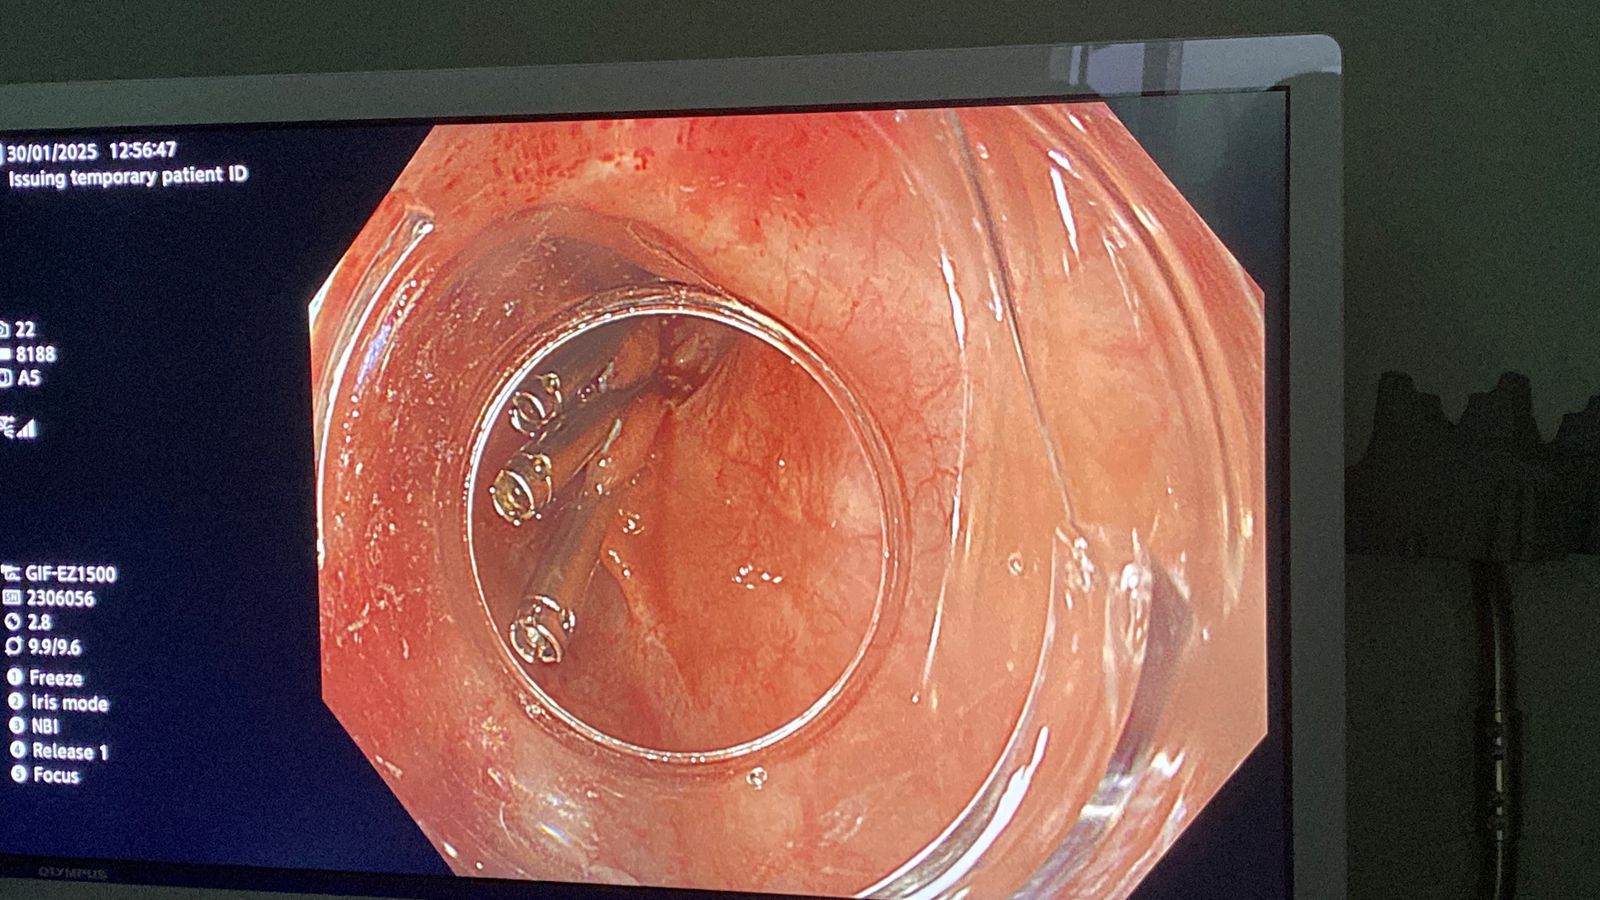

نجحت وحدة المناظير بكلية الطب في جامعة حلوان في إجراء أول عملية من نوعها باستخدام منظار الموجات فوق الصوتية لتشخيص واستئصال ورم بالمريء في نفس الجلسة. تمت العملية بمستشفى بدر الجامعي، دون الحاجة لأي تدخل جراحي، مما يمثل تطورًا كبيرًا في مجال الطب الحديث.

استغرقت العملية 30 دقيقة فقط، حيث تم استخدام تقنية مناظير الفراغ الثالث لتحديد نوع الورم، موقعه، وحجمه، ومن ثم استئصاله بنجاح في نفس الجلسة. هذا النهج الفعال ساعد في تجنب مضاعفات التخدير المتكرر، وتمكنت المريضة من مغادرة المستشفى في حالة صحية ممتازة بعد 24 ساعة فقط.

تمت العملية تحت إشراف الدكتور شريف البحيري، مدرس الباطنة العامة بكلية الطب واستشاري المناظير التداخلية، والذي تلقى تدريبًا متخصصًا في هذه التقنية المتقدمة في جامعة كاتب أتاتورك بتركيا، ضمن مهمة علمية بدعم من جامعة حلوان.